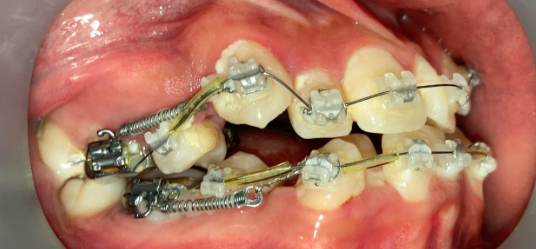

インプラントアンカー装着中の矯正治療経過|奈良の矯正歯科

アンカー装着中

インプラントアンカーで上の歯列全体を後方に移動。抜歯せずにガタガタと口元の突出感を改善しました。

ℹ️ ただし、この方法には限界があります。歯を後ろに動かせる量には上限があるため、口元の突出が大きい場合やガタガタが重度の場合は、非抜歯では対応できません。適応かどうかは精密検査で判断します。